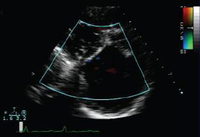

Doppler in a patient with pulmonary regurgitation following repair of tetralogy of Fallot. The patient has a restrictive right ventricle, and Doppler shows evidence of restriction with an antegrade ‘A’ wave in the pulmonary artery

From: Chaturvedi RR, Redington AN. Heart. 2007 Jul;93(7):880-9; used with permission